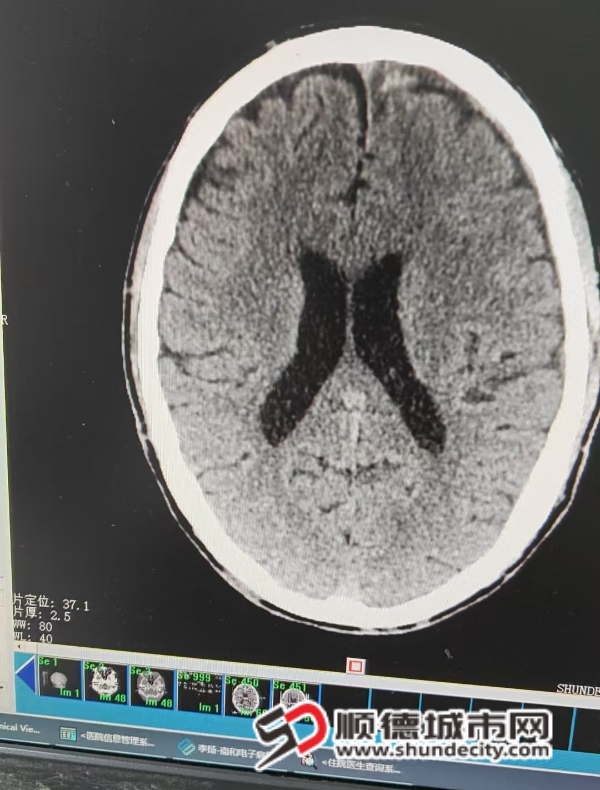

手术后。

头颅CT扫描是诊断慢性硬膜下血肿的金标准。能够快速、清晰地显示血肿的位置、大小、范围以及脑组织受压的程度。